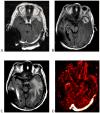

Neurologic complications of cancer are common and are frequently life-threatening events. Certain neurologic emergencies occur more frequently in the cancer population, specifically elevated intracranial pressure, epidural cord compression, status epilepticus, ischemic and hemorrhagic stroke, central nervous system infection, and treatment-associated neurologic dysfunction. These emergencies require early diagnosis and prompt treatment to ensure the best possible outcome and are best managed in the intensive care unit. This article reviews the presentation, pathophysiology, and management of the most common causes of acute neurologic decompensation in the patient with cancer.